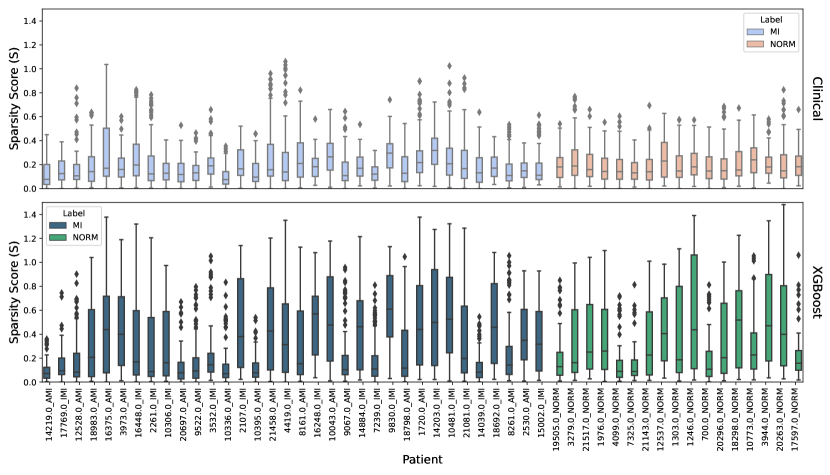

In terms of overall counterfactual sparsity, our clinical approach demonstrated lower sparsity (0.19) compared to the XGB feature, which had a sparsity of 0.33. For a clearer understanding of sparsity on individuals, please refer to Figure 6. Patient-wise differences can be observed by comparing clinical and XGB boxplots. The general sparsity in XGB is evident in the figure, although some cases displayed even lower sparsity than their clinical-weighted counterparts.